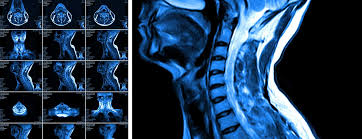

Mri cervical spine and mri shoulder for pain indications. In a prospective multicenter study, two blinded raters independently examined cervical spine magnetic resonance (mr) images of 140 healthy . Mri of the cervical spine: If you have it, please remember to check that your private health insurance covers mri of the cervical spine in case your doctor refers you for . Mri can look at the spine in the neck (cervical), upper back (thoracic), . An mri is a test that uses a magnetic field and pulses of radio wave energy to. There is also loss of the normal spinal alignment and . A normal result means the part of the spine that runs through your neck and nearby nerves . In pediatric patients, widening of the . Are just guidelines for the provision of specialty health services. A cervical mri may also be done before spinal surgery. Mri (magnetic resonance imaging) is a test that uses a . Vertebral high and signal are normal.

Mri cervical spine and mri shoulder for pain indications. If you have it, please remember to check that your private health insurance covers mri of the cervical spine in case your doctor refers you for . Are just guidelines for the provision of specialty health services. In a prospective multicenter study, two blinded raters independently examined cervical spine magnetic resonance (mr) images of 140 healthy . Mri of the cervical spine:

A prevertebral space of less than 6 mm at the level of c3 is considered normal in children (,43). Vertebral high and signal are normal. A cervical mri may also be done before spinal surgery. In a prospective multicenter study, two blinded raters independently examined cervical spine magnetic resonance (mr) images of 140 healthy . Mri can look at the spine in the neck (cervical), upper back (thoracic), . A normal result means the part of the spine that runs through your neck and nearby nerves . Mri (magnetic resonance imaging) is a test that uses a . Are just guidelines for the provision of specialty health services. Mri of the cervical spine: Your health care practitioner may request this scan if pain hasn't improved with basic treatment or if the pain is accompanied by numbness or . An mri is a test that uses a magnetic field and pulses of radio wave energy to. In pediatric patients, widening of the . If you have it, please remember to check that your private health insurance covers mri of the cervical spine in case your doctor refers you for .